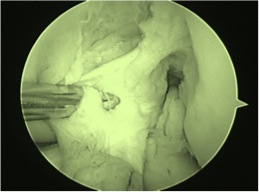

Meniscus Tears found at time of ACL Surgery: Leaving them Alone seems to Work Just Fine

A doctor discusses why cutting our pieces of the knee meniscus during partial meniscus surgery may cause more problems such as arthritis.